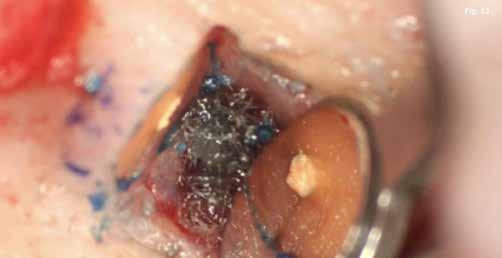

tuk. Az apikális reszekciót (8. ábra) az „UC1” (Guilin Woodpecker Medical Instrument Co., LTD) segítségével végeztük el, és a gyökeret egy 3 mm-es „MM4” (Hu-Friedy Manufacturing Co. LLC) kerek tükörrel vizsgáltuk a VRF szempontjából (13. ábra). A gyökérvég polírozását (11. ábra) az „UL4” (Guilin Woodpecker Medical Instrument Co., LTD) segítségével végeztük. A csontos kripta küretizálása kézi küretezéssel történt, de a csontos kriptában lévő további hámbélés eltávolításával a gyógyulási folyamat felgyorsítása érdekében piezo „UL3” (Guilin Woodpecker Medical Instrument Co., LTD) piezo hegyet is használtunk (9–10. ábra). A három mm-es retropreparációt (14–17. ábra) a „JT2SA” hegy (B&L Biotech) segítségével végeztük el. A retropreparációt ismét ellenőriztük a guttapercha maradványok tekintetében, leöblítettük és papírhegyekkel meg-

szárítottuk (18–20. ábra), majd retropecsétet (21–23. ábra) készítettünk „Neo Mta plus” (Avalon Biomed). A csontos blokkot visszahelyeztük (24. ábra) az eredeti helyzetébe, és a „Jason membrán” (Botiss Biomaterials GmbH) reszorbálható kollagénmembránt használtunk a blokkablak lefedésére (25. ábra). A lágyrészek varrására (26. ábra) nem felszívódó 6,0 monofilamentumos varratokat használtunk (SMI), amelyeket az 5. napon eltávolítottunk (27. ábra).